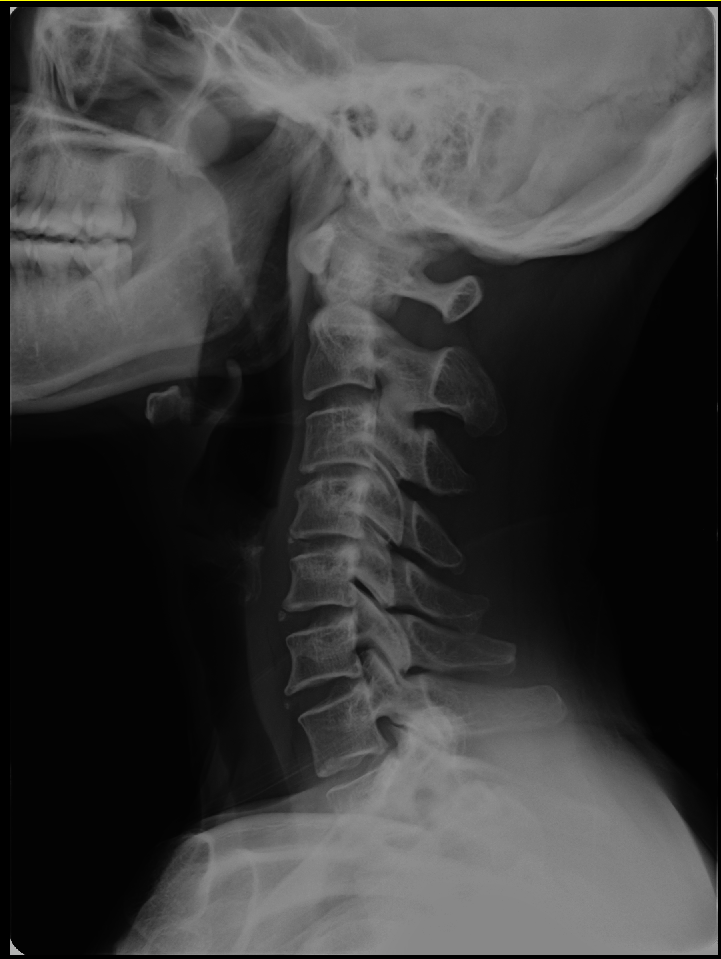

CBA장치를 이용한 턱관절 교정으로 일자목을 C커브로 바꾸세요 일자목은 경추 7번 이하의 모든 척추뼈들을 아래로 밀어낸다던지 척추 간 사이를 좁아지게 만드는 직접적인 원인 제공을 하게 됩니다. 목이 나빠지면 허리가 나빠지게 되고 허리가 나쁘다면 목이 아프지 않아도 목부터 C커브로 교정을 하지 않으면 평생 그 형태에서 계속 나쁘게 퇴행이 오고 허리디스크까지 만들게 됩니다. 허리디스크가 오는 원인이 경우에 따라서 다를 수 있지만 치료는 좁아진 디스크를 벌려야 한다는 것입니다.https://naver.me/FgiE6Sux

목이 C커브의 반대로 꺾여 있다면 일자목을 넘어서 역 C커브로 변형이 된 형태인 거죠. 늘 뒷목이 뻐근하고 등이 결렸다가 어깨가 아팠다가 두통이 있고 아침에 일어나면 뒷목이 뻐근하고 허리도 좀 아플 때가 있어요... 젊은 환자들이 이런 경우가 많고 항상 목을 꺾어보고 근육을 풀어보려고 하고 담은 한의원이니까 침치료받고 경추베개를 쓰고... 해도 전혀 치료에는 진전이 없습니다. 근육치료와 뼈치료는 엄연히 다른 것입니다. 이렇게 해서 역 커브가 C커브로 바뀌지 않는다는 것입니다. 경추가 옆으로 휜 것은 어떻게 할 건데요...? 10여 년 가까이 역커브, 일자목이 방치가 되면서 척추들은 계속 주저앉게 되고 어느 날 갑자기 허리가 삐끗하거나 목에서 디스크 초기 진단까지 가면서 디스크 환자의 대열에 들어갑니다. 지금까지는 운동 잘하고 침치료받고 하는 수준의 환자였는데 이제부터는 대형 척추병원에서 치료받아야 하는 책임감을 환자들이 느낍니다. 척추의 변형과 주저앉는 것을 평생 치료해야 하는 일이 된다면 이 얼마나 경제적으로 시간적으로 낭비입니까.https://naver.me/FgiE6Sux

일자목을 C커브로 바꾸면 좁아진 허리디스크 공간도 벌어지게 됩니다. 그러기 위해서는 경추 1,2번과 턱관절교정을 이용한 CBA교정 치료를 받아야 합니다. 치아교정, 턱관절치료는 절대적으로 심미적인 치료가 목적이 되어서는 안 되는 것입니다. 척추와 턱관절이 기능적으로 움직이는데 문제가 없게 턱관절 교정을 하고 난 후 마지막으로 교정을 해야 합니다. 턱관절치료가 안 돼서 고생인 환자들 목, 허리 치료가 안 돼서 고생인 환자들 모두가 경추 1,2번은 절반은 빠져있다는 것, 턱관절이 경추 1,2번을 비틀게 한다는 것을 모르고 허리 아프면 허리치료 턱 아프면 치과 치료만 받아서 효과도 없고 부작용에 고생을 하고 있는 것입니다. 환자들이 근육을 키우는 PT를 하거나 마사지를 받거나 경추베개를 베고 자거나 하면 될 거 같이 생각하고 병원 가면 누구나 일자목은 있어요 하고 넘어가고 혹은 도수치료받고.. 전혀 치료가 되지 않습니다. 일자목 치료를 무슨 스포츠, 운동의 하나로 생각하는 분들 있는데요 반드시 경추교정을 제대로 받지 않으면 C커브가 되지 않는다는 것. 아직까지 이렇게 해서 일자목 좋아지는 경우를 본 적이 없습니다. 부정교합이나 턱관절이 맞지 않으면 해부학적으로도 빠져있는 목은 더 비틀리게 됩니다. X-ray 찍으면 그냥 하는 말만 듣지 마시고 어떻게 하면 C커브로 바뀔 수 있는지 따져 보세요. 꾸준히 관리와 운동은 치료가 아닙니다. 2,3개월 교정을 받으면 C커브로 바뀌어야 합니다. 경추 1,2번과 턱관절 교정을 CBA로 받아야 그러한 변화를 줄 수 있습니다. 제가 미처 모르는 어떠한 운동이나 자세치료를 받고 정말 C커브로 경추가 바뀌었다면 X-ray 검사로 다시 재확인이 되어야 하고 허리의 통증도 줄어야 합니다. 신도림동 터커리한의원에서 CBA를 이용한 턱관절교정을 받았을 때 가장 큰 변화는 일자목이 C커브로 바뀌는 것입니다. 그다음에 사경증도 좋아지고 측만증, 허리디스크까지 점점 아래로 척추변화가 이루어집니다. 척추교정은 골반으로 하는 것이 아니고 목부터 해야 하고 반드시 X-ray, MRI 검사 확인을 받으세요. 통증이 많이 줄어서 만족을 하시는 것도 매우 좋은 일이지만 검사 확인을 추천드립니다. 환자마다 치료기간과 만족도는 척추 상태에 따라 달라지는 이유도 여기에 있습니다. 모든 치료에는 부작용도 있을 수 있으니 꼭 X-ray, MRI 검사를 지참하시고 내원하시기 바랍니다.https://naver.me/FgiE6Sux